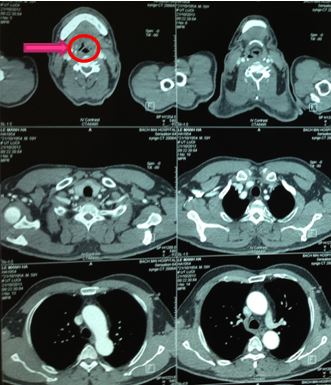

Chụp cắt lớp vi tính 64 dãy cổ - ngực sau xạ trị 40 Gy:

Hình 5. Hình ảnh chụp cắt lớp vi tính vùng cổ sau điều trị xạ trị 40Gy và 2 đợt hoá trị

+ Vị trí gốc lưỡi bên trái nắp thanh môn có nốt kích thước 16x13x12mm; ngấm thuốc mạnh sau tiêm, thâm nhiễm nhẹ vào bờ trái nắp thanh môn gây dày nhẹ nắp thanh môn. Không thấy hạch to vùng cổ và hạch to trung thất.

+ Phối phải: Dày tổ chức kẽ dưới màng phổi phía sau vùng đáy phổi, không thấy tổn thương dạng nốt hoặc dạng khối. Khối thấy giãn phế quản, phế nang.

+ Phổi trái: nhu mô phổi thùy dưới vị trí dưới màng phổi có vài nốt tăng tỷ trọng nhỏ dạng tổn thương tổ chức kẽ, nốt lớn nhất đường kính 4mm kèm theo dày tổ chức kẽ dưới màng phổi phía sau vùng đáy phổi, không thấy giãn phế quản, phế nang.

+ Dày khu trú màng phổi vùng đáy phổi hai bên.

+ Kết luận: Hình ảnh nốt gốc lưỡi bên trái kích thước giảm so với phim chụp trước, thâm nhiễm nhẹ nắp thanh môn bên trái, tổn thương nốt tổ chức kẽ sát màng phổi thùy dưới phổi hai bên.